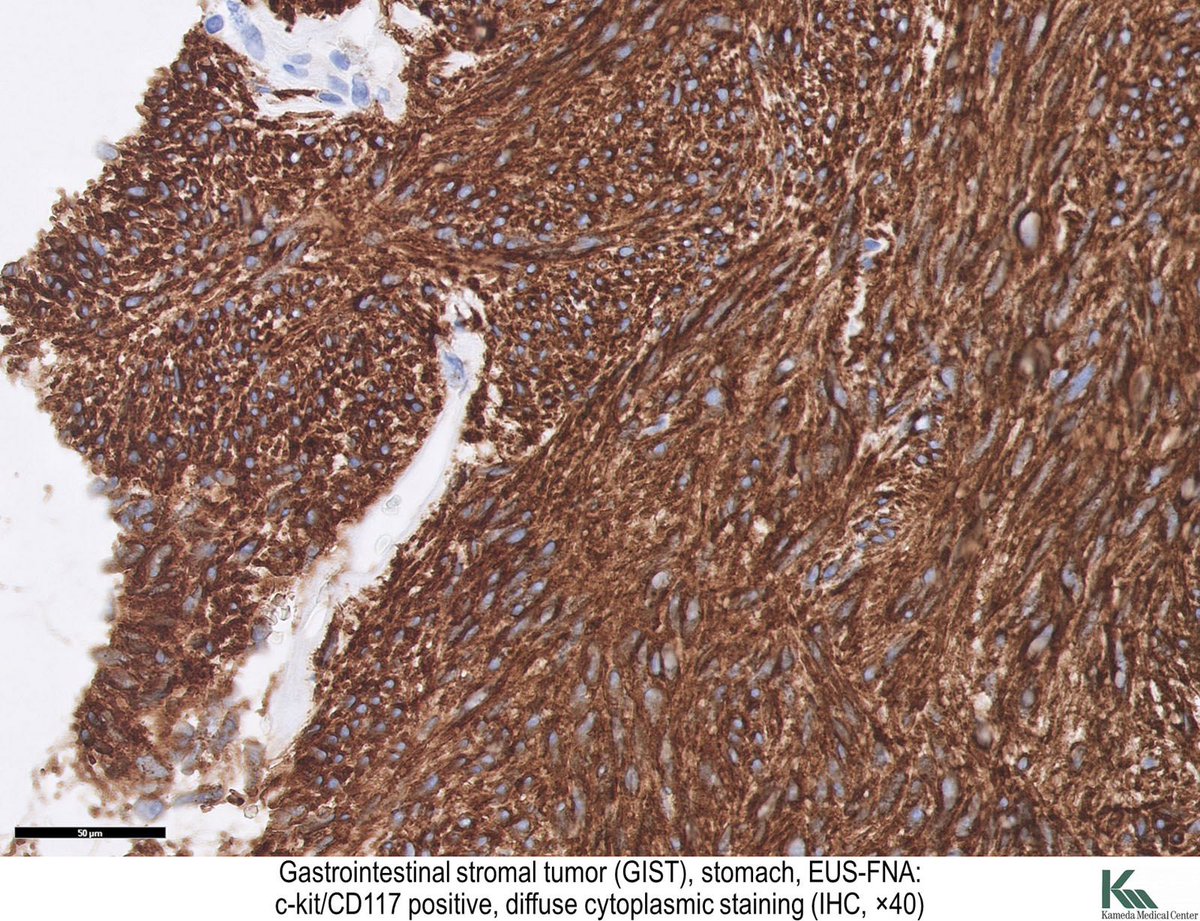

خلاياها تشبه الى حد كبير الخلايا العضلية و لكن في شكل مغزلي (spindle). و يتم تحديدها ببعض الصبغات المناعية مثل ckit/CD117 كما هو موضح في الصور